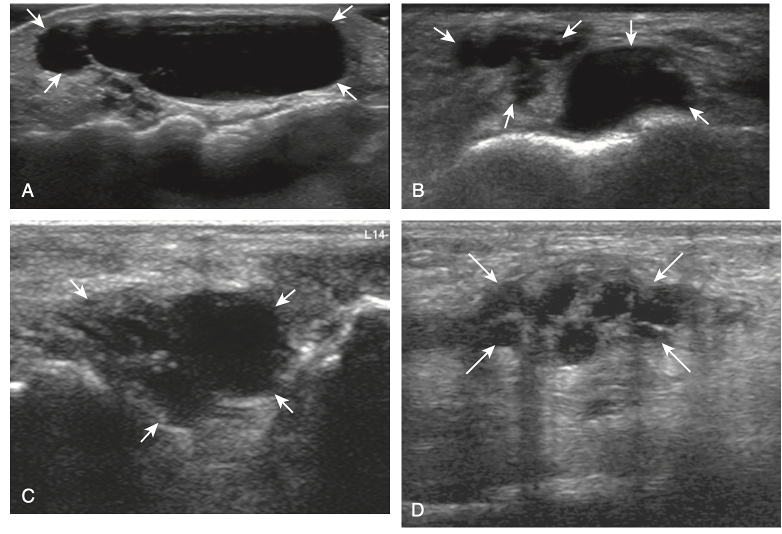

Which of the below is a ganglion cyst on US

Trick question! All of the above!

Ganglion cysts have several appearances at ultrasound. The most common appearance is that of a hypoechoic or anechoic, multilocular or multilobular, noncompressible cyst that may look complex.

Smaller ganglion cysts are more likely hypoechoic and may show only limited increased through-transmission.

The multilocular appearance of a cyst is specific to both ganglion cysts and fibrocartilage cysts (parameniscal and para- labral); the location of the multilocular cyst assists in this diagnosis. If in contact with fibrocartilage, then parameniscal or paralabral cyst is likely. If located superficial to the scapholunate ligament (Fig. 2.66), near the radial artery at the wrist (a very common site), at the sinus tarsi of the ankle, or within the Hoffa infrapatellar fat pad or at the gastrocnemius tendon origin at the knee, ganglion cyst is likely. The other appearance of a ganglion cyst is a unilocular fluid collection, which can be associated with wrist, hand, ankle, and foot tendons. Unlike a bursal fluid collection, such unilocular ganglion cysts are usually not compressible and not in a location of an expected bursa. Aspiration should only be attempted with a larger diameter needle (such as a 16- or 18-gauge needle), given the high viscosity of the gel-like fluid.